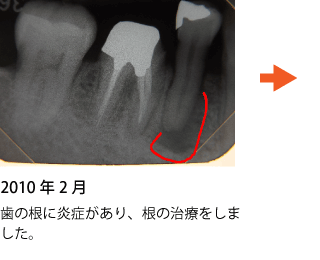

重度の虫歯で歯の神経まで侵されている場合、ダメになった神経を取り除く治療をします。

これは歯を残すための最後の治療、保存治療です。